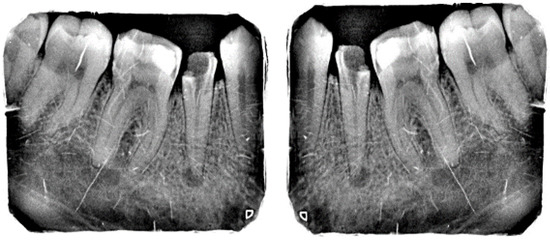

| Lesion Type | Training Data | Test Data |

|---|---|---|

| Primary Endo with Secondary Perio | 104 | 18 |

| Primary Endodontic Lesion | 105 | 19 |

| Primary Perio with Secondary Endo | 33 | 06 |

| Primary Periodontal Lesion | 100 | 18 |

| True Combined Lesions | 111 | 20 |

| Total radiographs | 453 | 81 |

| Total X-rays after data augmentation | 1359 |